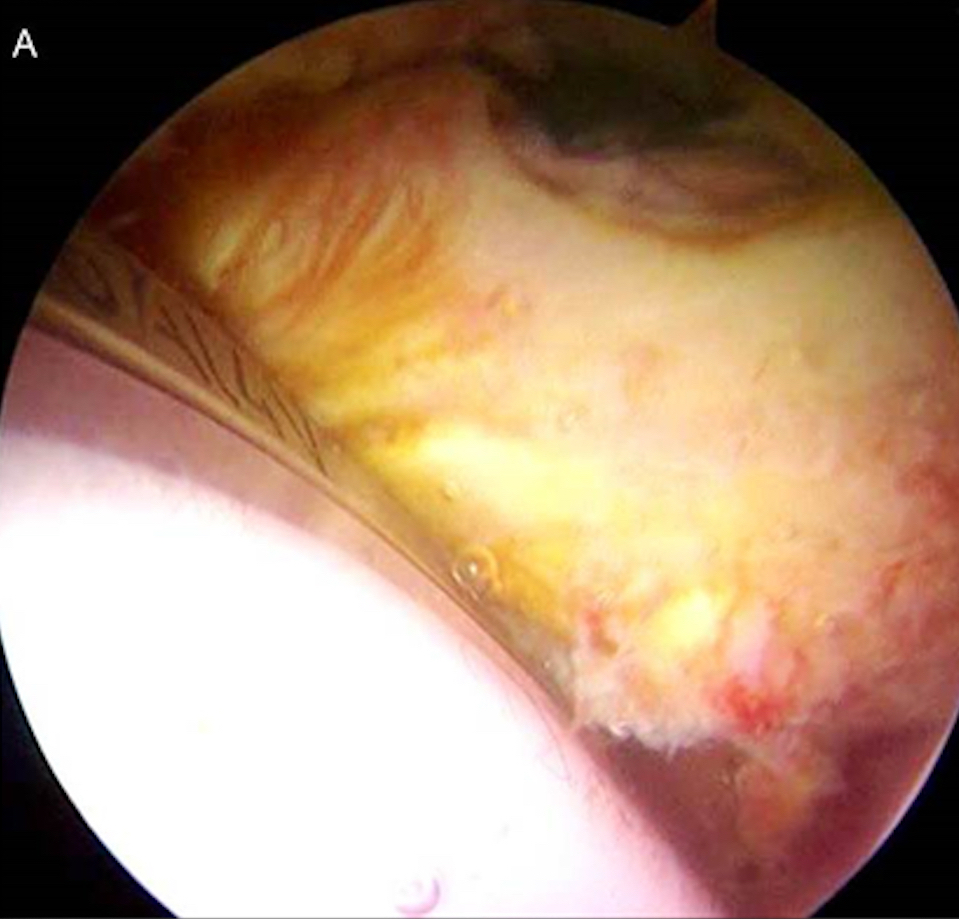

Cosa curiamo con l’atroscopia d'anca - Il conflitto del tendine Psoas con la Coppa Acetabolare nelle protesi d’anca dolorose

Questa è una patologia che colpisce alcuni pazienti (circa 0,5% - 3%) portatori di protesi totale d’anca, quando la coppa acetabolare viene posizionata con sporgenza eccessiva anteriore. Questa sporgenza comporta lo sfregamento del tendine Psoas (muscolo flessore dell’anca) sulla protesi, creando dolore nel flettere attivamente la coscia (dolore nell’entrare in auto, nel salire le scale, nel portare la gamba sul letto), costringendo il paziente ad accompagnare l’arto con le mani.

Il trattamento artroscopico consiste nell’eseguire il Release del tendine (senza toccare la protesi) apportando immediato sollievo al paziente (Fig.5a e 5b).